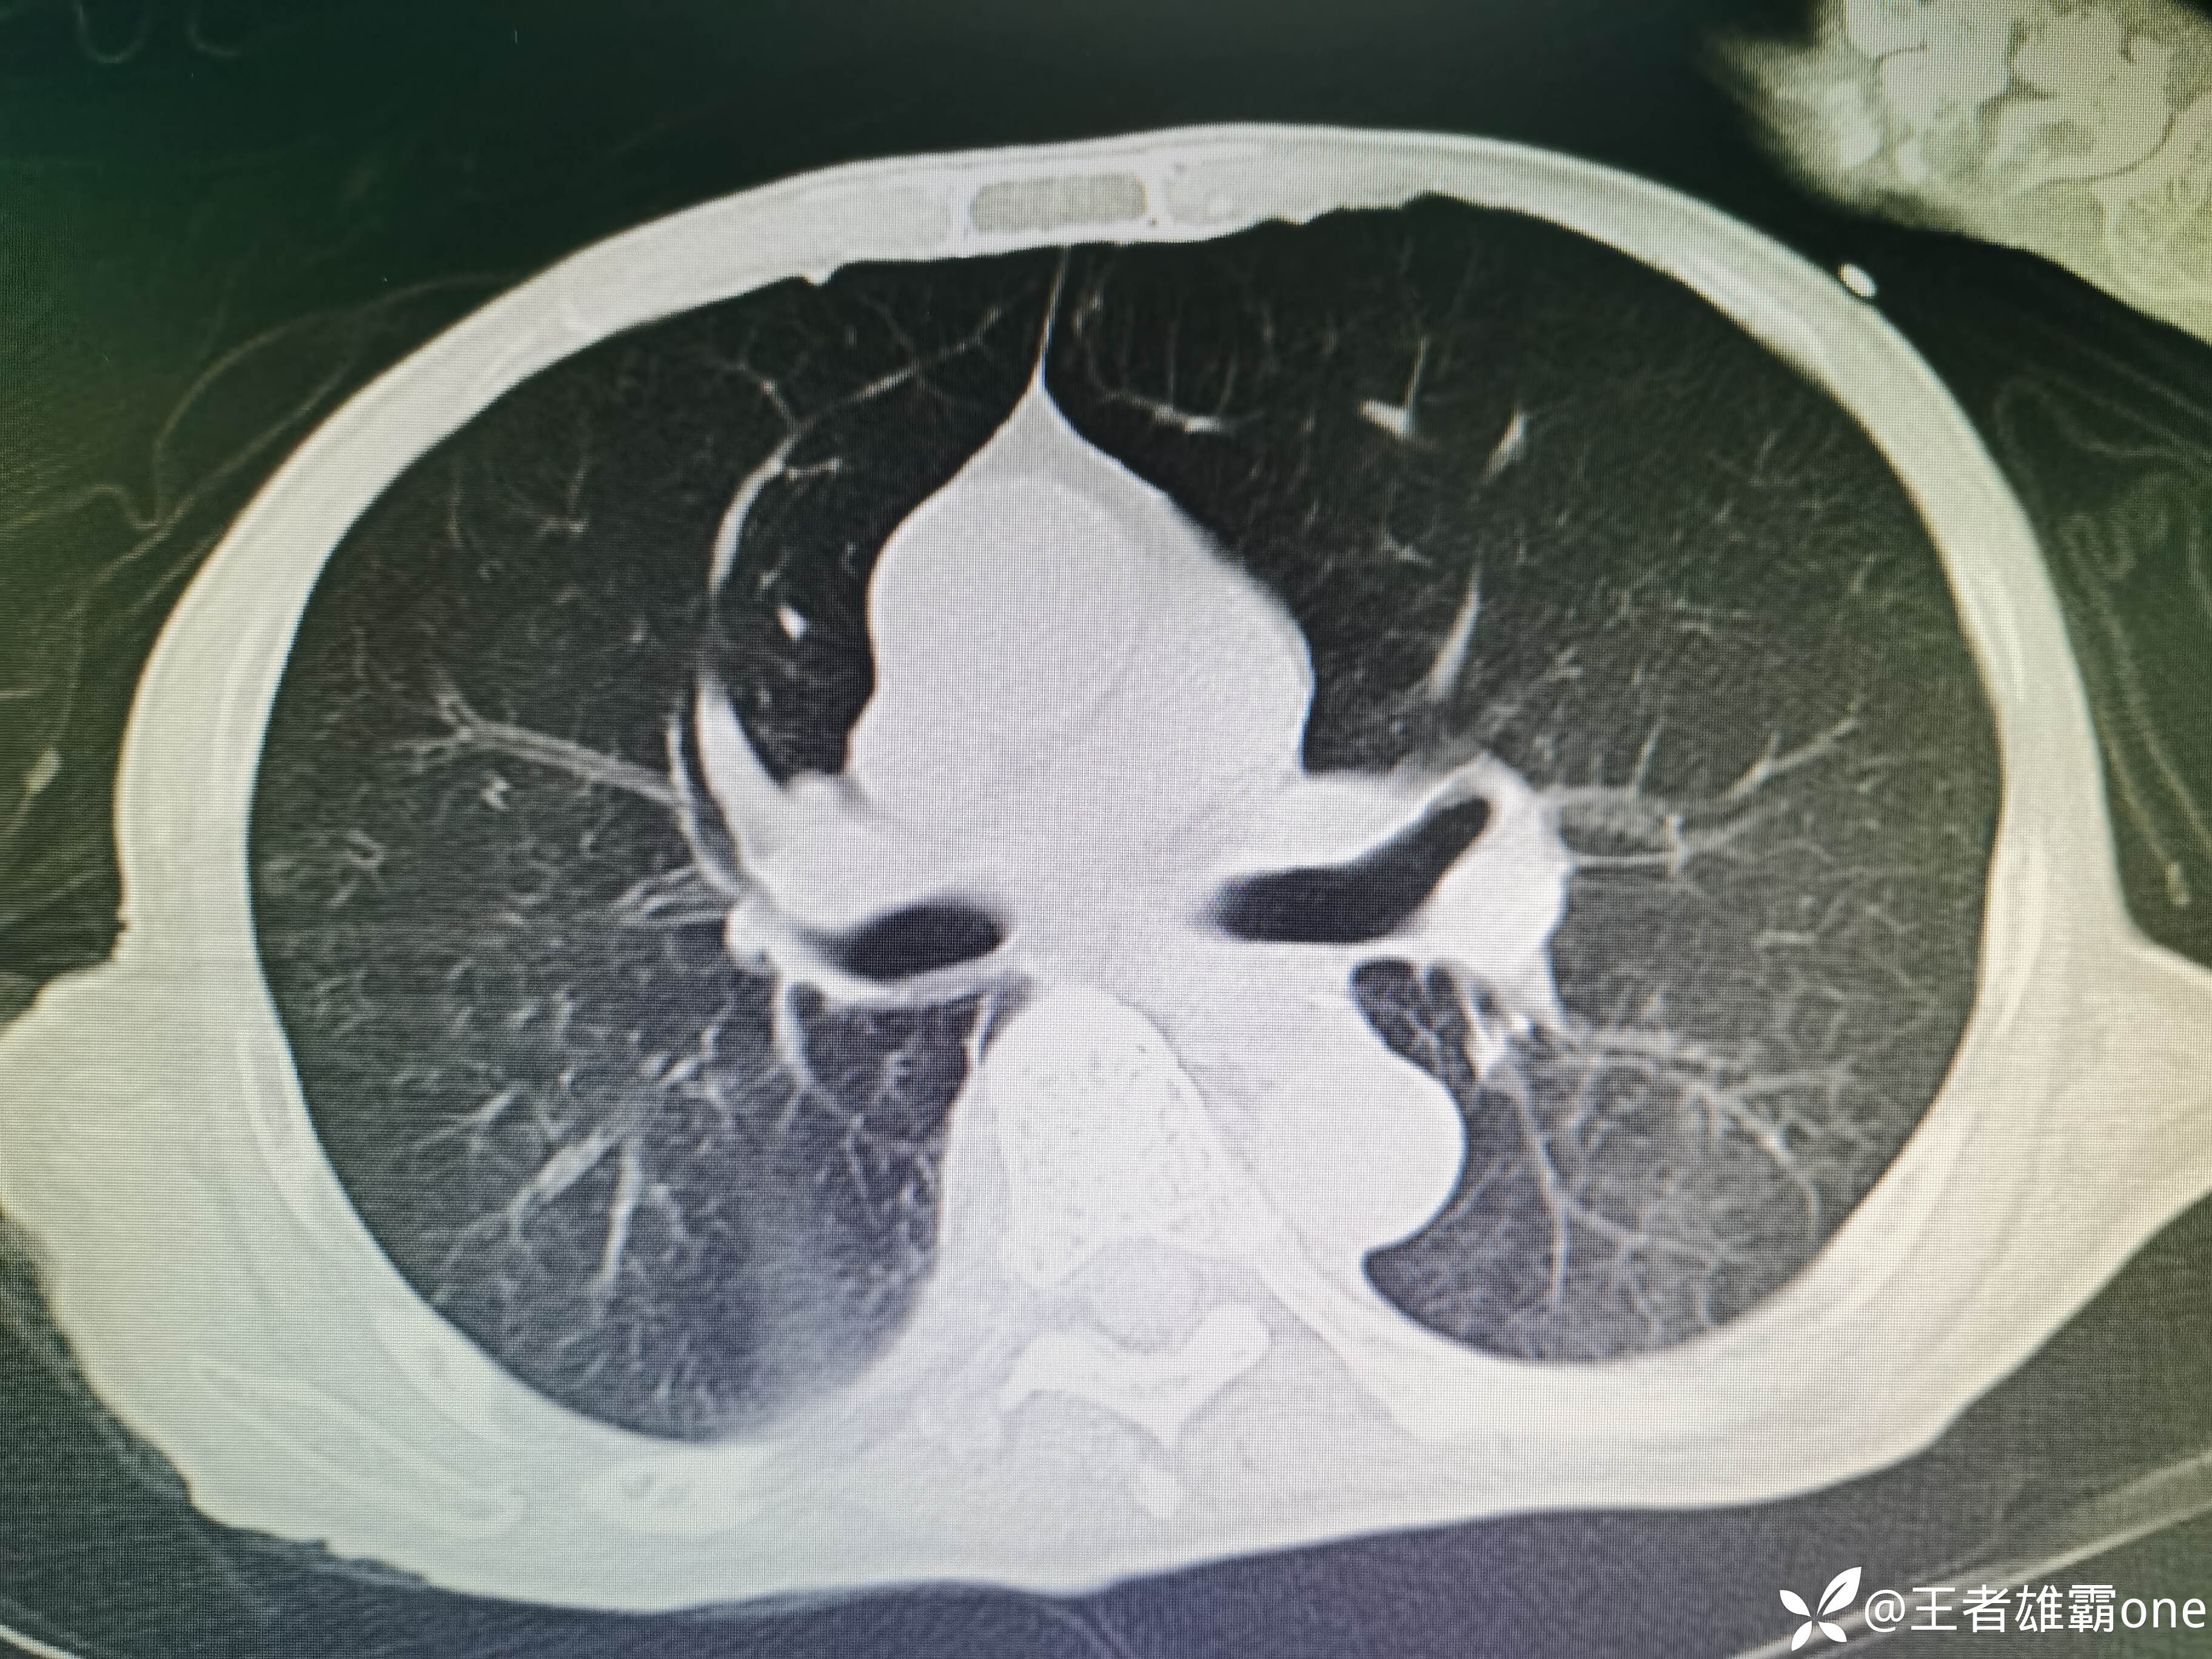

入院时胸部CT:

具体图片: